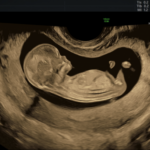

ÉCHOGRAPHIE PENDANT LA GROSSESSE

Au cours de la grossesse, des échographies de dépistage anténatal vous seront proposées en cas d’évolution...